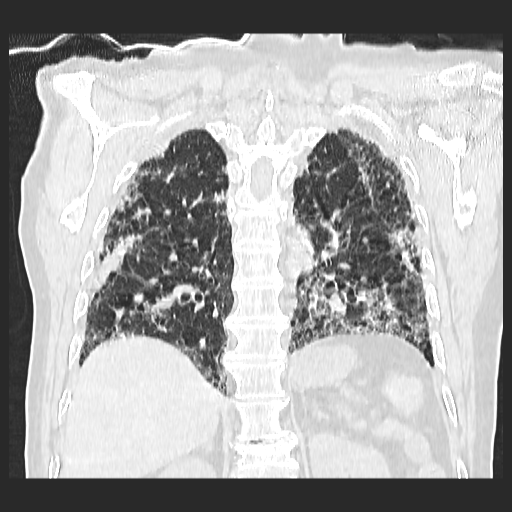

El parénquima pulmonar izquierdo muestra un infiltrado intersticial difuso que causa engrosamiento del septum axial, además del fenómeno de bronquiectasias quísticas se observan pequeñas bulas enfisematosas de localización subpleural que compromete ambas bases pulmonares.

Se observan imágenes de vidrio despulido en todo el lóbulo inferior izquierdo, el cual compromete los segmentos de la língula del segmento superior y medio

El parénquima pulmonar derecho muestra infiltrado intersticial en imagen de vidrio despulido con evidencia de lesiones subpleurales que representan bullas enfisematosas de diferentes tamaños.

Al utilizar un contraste Minip, se observan bronquiectasias cilíndricas en el extremo del lóbulo superior derecho, observándose un patrón de panal de abeja situada en la región apical del lóbulo superior izquierdo.

Bronquiectasias cilíndricas, bullas enfisematosas basales bilaterales